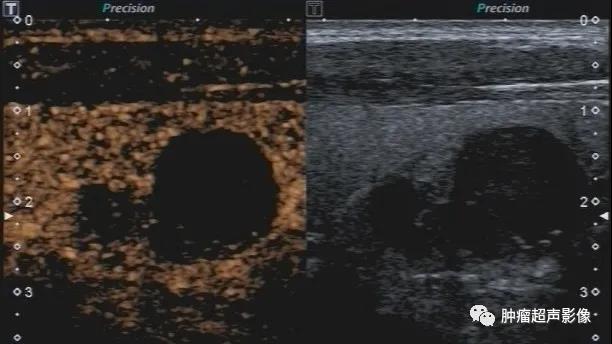

甲状腺下极结节,病史不明,呈低回声,边缘光整,呈双环征(周边低回声晕),内部无血流,采用超微血流成像显示内部无血流,呈“黑洞征”,从而增加诊断皱缩结节的信心,避免穿刺及手术。